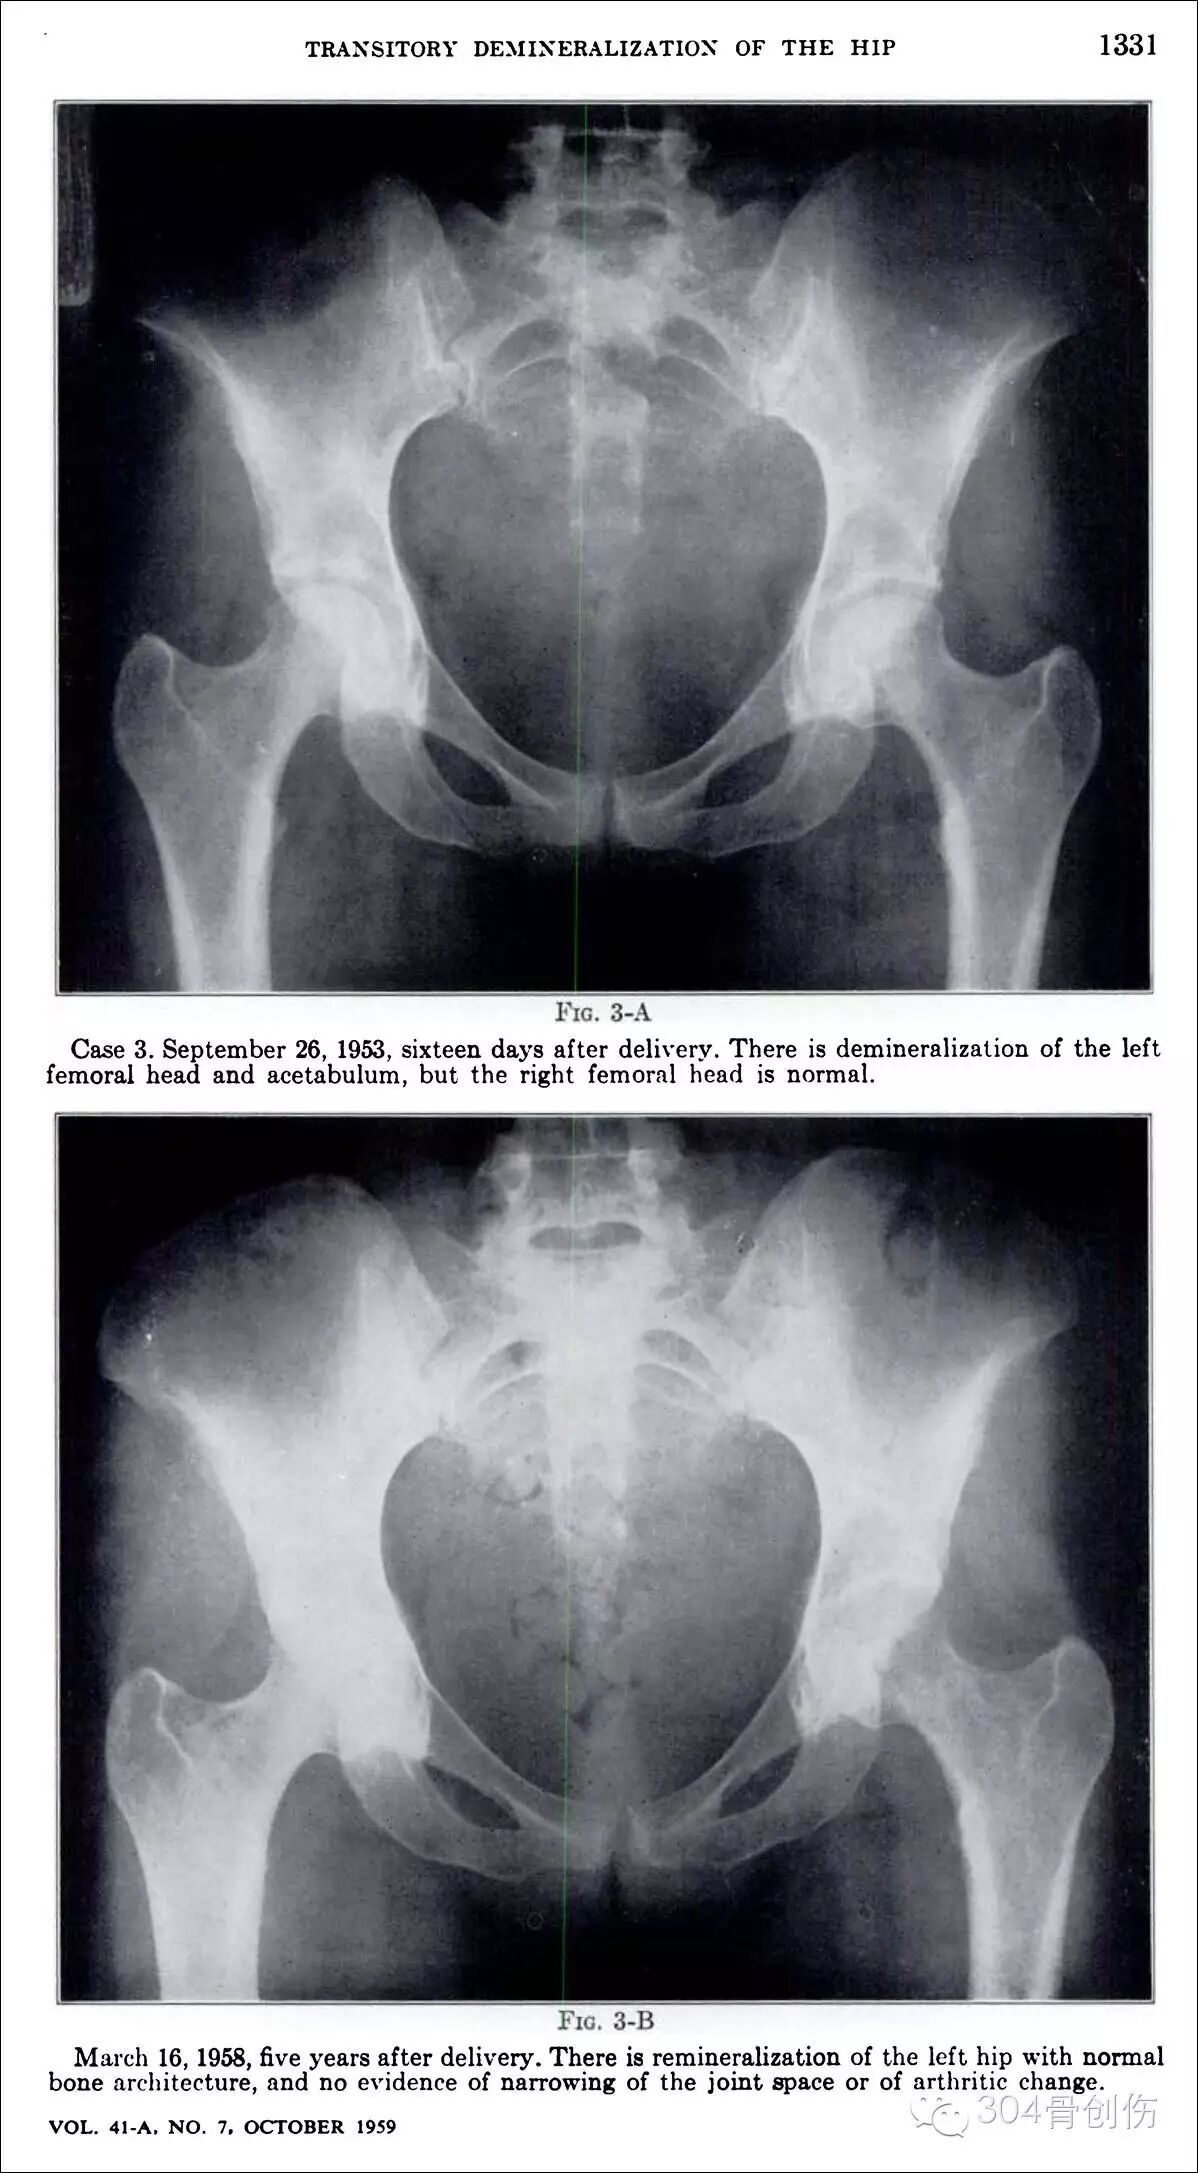

髋部一过性骨质疏松症(transient osteoporosis of the hip, TOH)是出现于妊娠晚期的一种罕见的骨代谢紊乱状况,其病因不清楚,表现为髋部疼痛及活动受限,可在髋关节X线上观察到明显骨量减少,1959年Curtiss教授首次报道(图),2005年国内郭依廷医生首次报道(图),综合发病过程,定义为“妊娠期一过性骨质疏松症”,不完全统计:全世界报道大约100余例,多为脊柱骨折,双侧股骨颈骨折少见,陈旧股骨颈骨折处理极为困难,目前缺乏大宗相关文献报道。

怀孕期间会骨折吗?-怀孕期

图-1959年Curtiss首次报道

1.Curtiss PH Jr, Kincaid WE. Transitory demineralisation of the hip in pregnancy. A report of three cases. JBJS(A),1959 ; 41: 1327~1333.